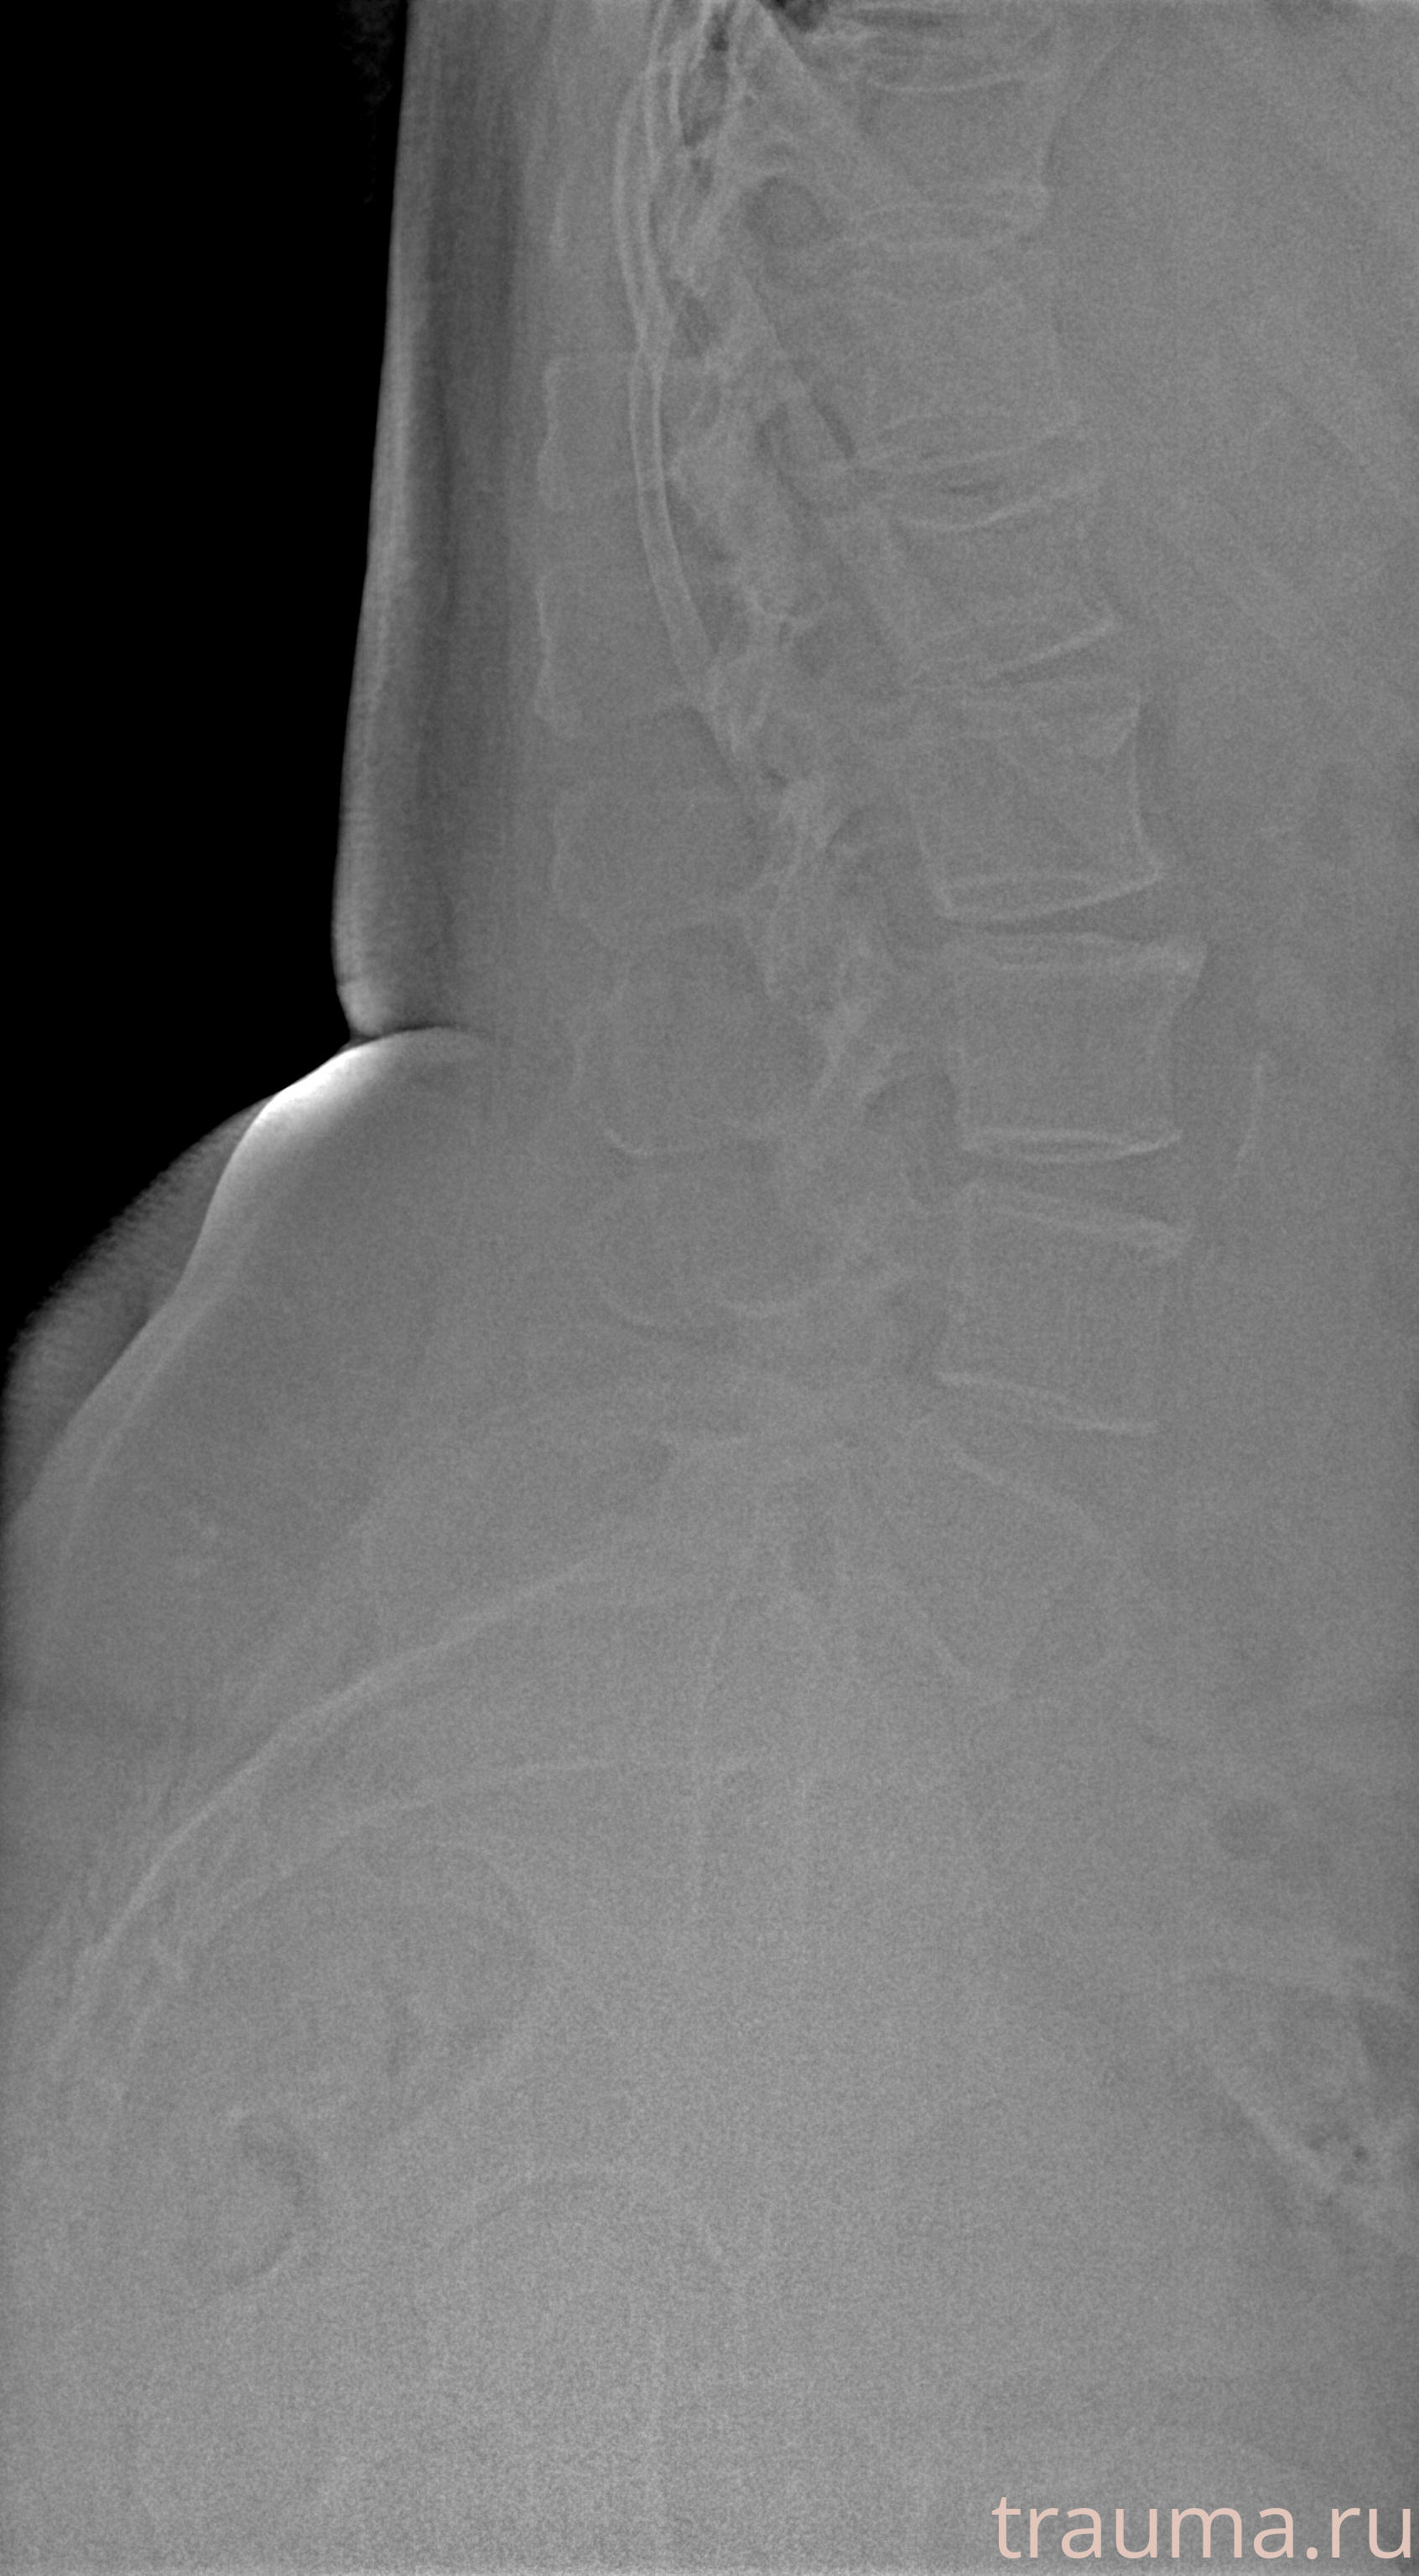

Рентгенограммы

Рентген на дому: по вашему адресу приезжает врач-рентгенолог, травматолог-ортопед с мобильным рентгеновским аппаратом, проводит диагностику травмы или заболевания, делает необходимые рентгенограммы, дает рекомендации по дальнейшему лечению. Получить качественные снимки в домашних условиях возможно благодаря уникальной методике, разработанной МосРентген Центром для института  Склифосовского